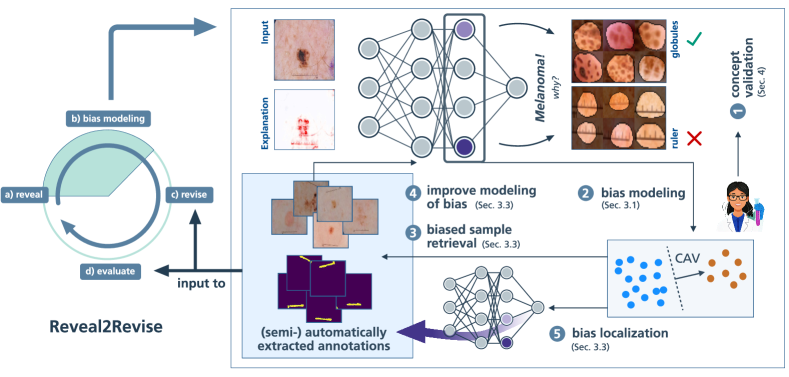

The field of XAI sheds light onto the previously non-transparent prediction behavior of DNNs, providing insights into their internal reasoning. While traditional local XAI methods focus on feature importance for individual predictions, global XAI approaches and mechanistic interpretability aim to understand overall model behavior by explaining the roles of internal representations and encoded features [1, 34, 79]. Recently, these insights have been utilized to systematically uncover model weaknesses like shortcut behavior. Current methods either detect outlier explanations for biased data samples [48, 3, 27] or outlier model concept representations [16, 53, 59]. Beyond revealing model weaknesses, XAI is also capable of identifying data-related issues causing the undesired behavior. Most related to our work, the iterative Reveal2Revise framework [59] consists of the four steps (a) bias revealing, (b) bias modeling, i.e., learning accurate bias representations, (c) model revision to unlearn shortcuts, and (d) re-evaluation. However, while it primarily focuses on model revision, it provides limited insights into bias revelation and modeling steps. This can lead to imperfect bias representations, limiting the effectiveness of the mitigation step. To fill this gap, we enhance the Reveal2Revise framework by providing a robust methodological foundation for the bias revelation and modeling steps to (semi-)automatically annotate and enrich datasets, leveraging insights from XAI, as illustrated in Fig. 1. Specifically, we discuss bias identification from both data and model perspectives, ( ) enabling expert-guided validation of model behavior. Moreover, ( ) we learn a model-internal bias representation, referred to as bias model, from an initial set of biased samples using Concept Activation Vectors (CAVs). We then ( ) introduce the retrieval of biased data samples using the learned bias model, ( ) enabling its iterative improvement. Furthermore, ( ) using the refined bias model for spatial bias localization, we enrich the dataset with extracted sample- and pixel-level annotations, which are used in the bias mitigation and evaluation steps of the Reveal2Revise framework to improve the generalization capabilities of AI models.

3 From Bias Modeling to (Semi-)Automated Data Annotation

In recent years, the XAI community has shifted its focus from local to global explanations to better understand overall model behavior. This line of research, known as mechanistic interpretability, aims to interpret internal representations in terms of human-understandable concepts, encoded as individual neurons, model circuits, or directions in latent space. Understanding model internals enables the identification of model substructures that encode biases stemming from data artifacts (step ( ) in Fig. 1). In this section, we discuss how biases are encoded within DNNs, and how this understanding can be utilized for data annotation tasks, such as the detection of biased samples and (spatial) bias localization. Note that while we assume knowledge on the existence of biases in this section, the identification thereof (step ( ) in Fig. 1) is addressed in Sec. 4.

Concept representations can be refined iteratively by correcting labeling errors in the data (step ( ) in Fig. 1). Specifically, non-artifactual and unknown samples with high bias scores are subject to manual inspection to improve the label quality and concept representation, as shown in Fig. 3. Starting with ( ) a small set of bias samples obtained from bias identification methods, ( ) an initial CAV is fitted. Next, ( ) manual inspection of samples with high bias scores improves the label quality. The updated labels are used to ( ) iteratively refine the CAV, ( ) resulting in a set of annotated bias samples.

4 Concept Validation: Detecting Spurious Behavior